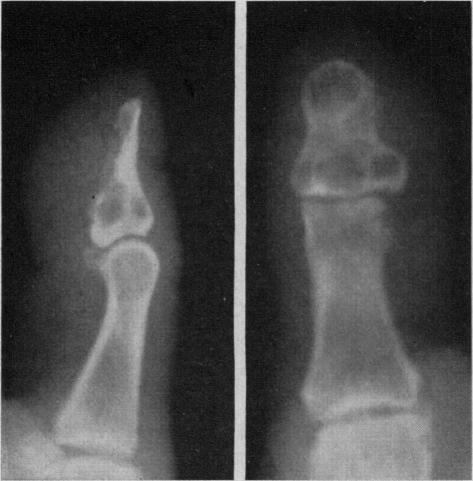

EPIDERMOID CYST OF THE TERMINAL PHALANX OF THE THUMB.

Can Med Assoc J. 1964 Jun 27;90(26):1464-6.